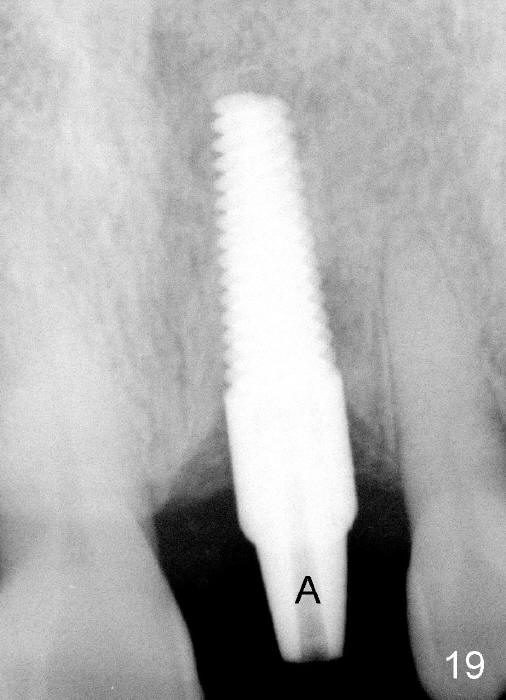

A 60-year-old lady had an abscess mesial to #9 six years ago (Fig.1,2 <), treated as a perio lesion by laser (Fig.3) and osseous surgery without bone graft (Fig.6, followed by CT exam revealing semi-circumferential bone loss (Fig.4,5). When the perio treatment failed, attention was paid to endo aspect (Fig.7-9). In fact the pulp was found to be vital when access to root canal therapy was made. As expected, the treatment failed again. The palatal fistula persisted. The infection was suspected to be a source of remote immediate implant site (#30). The tooth #9 was extracted. It appears that there is a semilunar crack line in the linguomesial root (Fig.12). When the socket healed 2 weeks post extraction (Fig.10), the #30 buccal defect was debrided with bone graft. There was no bone resorption 4 weeks post extraction (Fig.11); a 4.5x17 mm implant was placed (Fig.13-15). An immediate provisional was fabricated (Fig.16-18). Fig.19,20 were taken 3 months post implantation and 7 months post cementation, respectively. Dense bone forms around the implant coronally 4 years 5 months post cementation (Fig.21), while the gingiva is healthy palatally (Fig.22) and buccally (Fig.23).